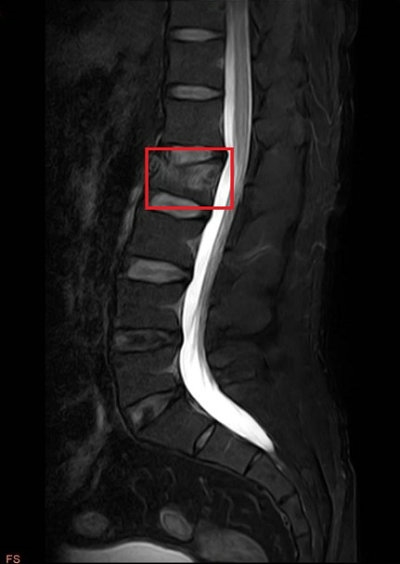

一位41岁中年男性高处坠落后出现腰部疼痛,不敢站立及扭动腰部,遂至郑州大学第五附属医院骨科一病区就诊,入院后迅速完善了X线、MRI等检查(A、B)。骨科一病区徐明杰科主任带领医护团队查房,对患者进行细致查体并查看患者检查结果后指出:患者腰2椎体新鲜压缩骨折(压缩超过1/3),与患者沟通可行“经皮椎弓根钉内固定术”治疗。患者了解到该手术方式不仅创伤小,且可部分恢复椎体高度、减短卧床时间,决定手术治疗。

B.术前MRI检查(L2新鲜骨折)